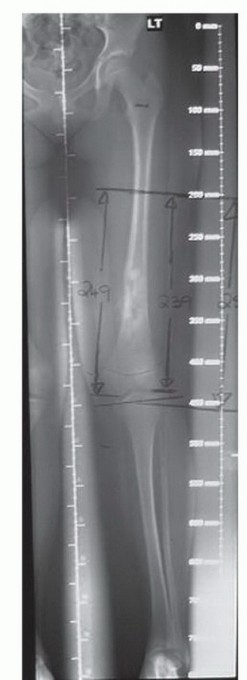

- التصوير المتقدم: يتم إجراء أشعة رنين مغناطيسي (MRI) وأشعة مقطعية (CT) مفصلة للورم والعظم المحيط لتخطيط الجراحة بدقة فائقة، وتحديد هامش الاستئصال الآمن.

- التخطيط الجراحي: يقوم الأستاذ الدكتور هطيف والفريق الجراحي بتخطيط دقيق لكل خطوة من خطوات الجراحة، بما في ذلك تحديد نوع الطرف الصناعي القابل للتمدد وحجمه، ومسار الشق الجراحي، وكيفية إعادة بناء الأنسجة الرخوة.

إذا أصاب الورم العظمي منطقة قريبة من صفيحة النمو، فإن استئصال الورم قد يتطلب إزالة جزء من هذه الصفيحة. هذا يؤدي إلى:

* توقف النمو في الطرف المصاب: بينما يستمر الطرف السليم بالنمو بشكل طبيعي.

* تفاوت في طول الأطراف (Limb Length Discrepancy): مما يؤدي إلى مشاكل في المشي، وآلام في الظهر والمفاصل، وحاجة مستمرة لارتداء أحذية خاصة أو إجراء جراحات إطالة متكررة.